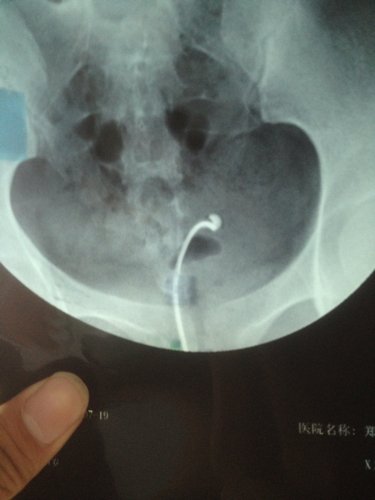

帮我看看这个X光照影,输卵管通不通?粘连吗? 点击展开 匿名用户 2014-07-22 10:32 为您推荐: 其他回答 你好,这个不一定的,平时的时候亲最好让大夫详细的检查一下比较放心的哦,平时多注意休息 斑驳的流年88 2014-07-22 10:35 相关问题 郑州怎么查输卵管通不通?输卵管不通粘连 我吃了活血化瘀的中药左侧附件隐隐作痛是什么原因呢(曾宫外孕切除了右侧输卵管)(现在左侧伞端粘连不通 子宫右倾,宫劲宫腔重度粘连,右侧输卵管不通??